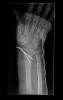

Carpo normal